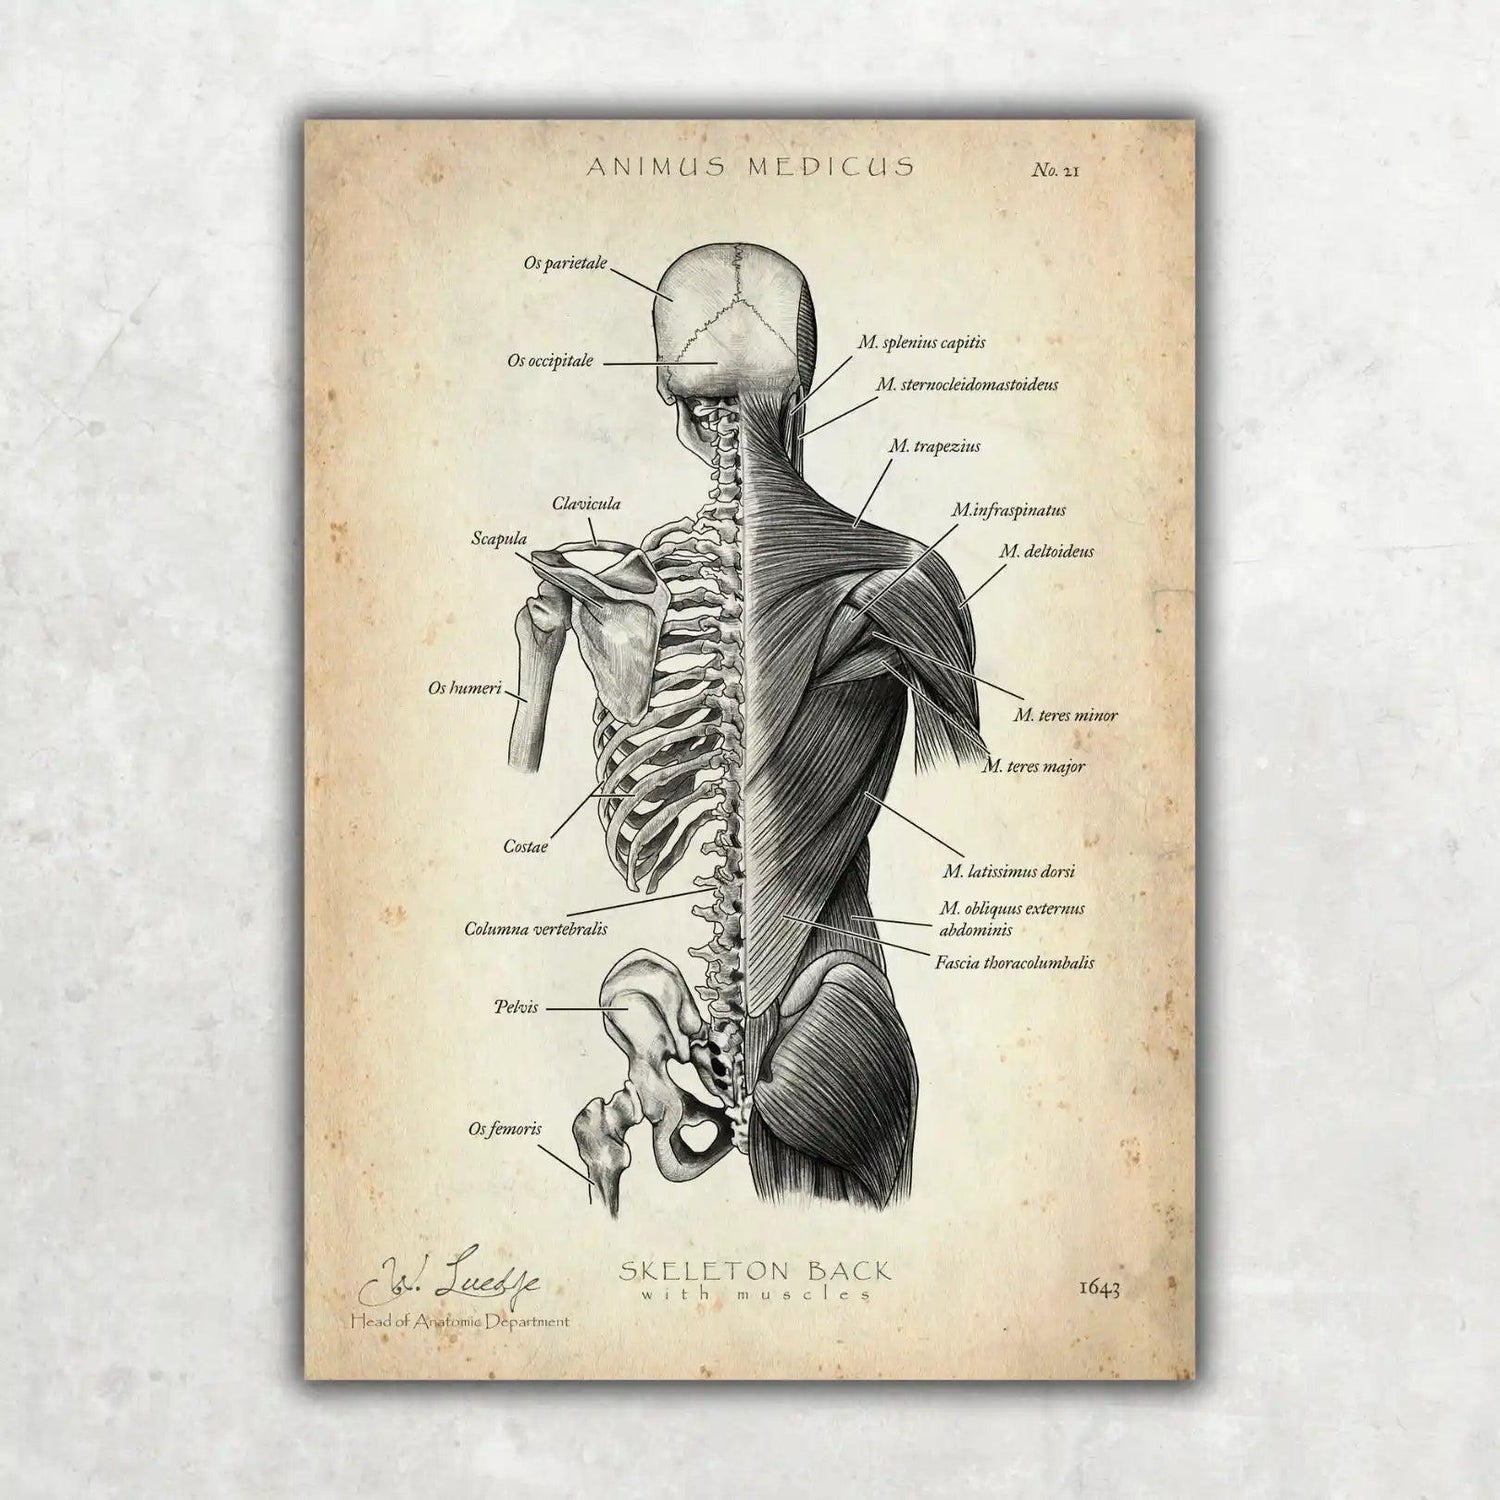

Warst du auf der Suche nach einer Möglichkeit, die faszinierende Anatomie des Herz-Kreislauf-Systems nicht nur zu lernen, sondern auch visuell zu erleben? Bei Animus Medicus findest du ästhetische Anatomie-Poster im Vintage-Stil, die medizinisches Wissen und kunstvolles Design perfekt vereinen. Entdecke jetzt unsere Kollektionen auf https://animus-medicus.de und bringe die Schönheit der Anatomie an deine Wände.